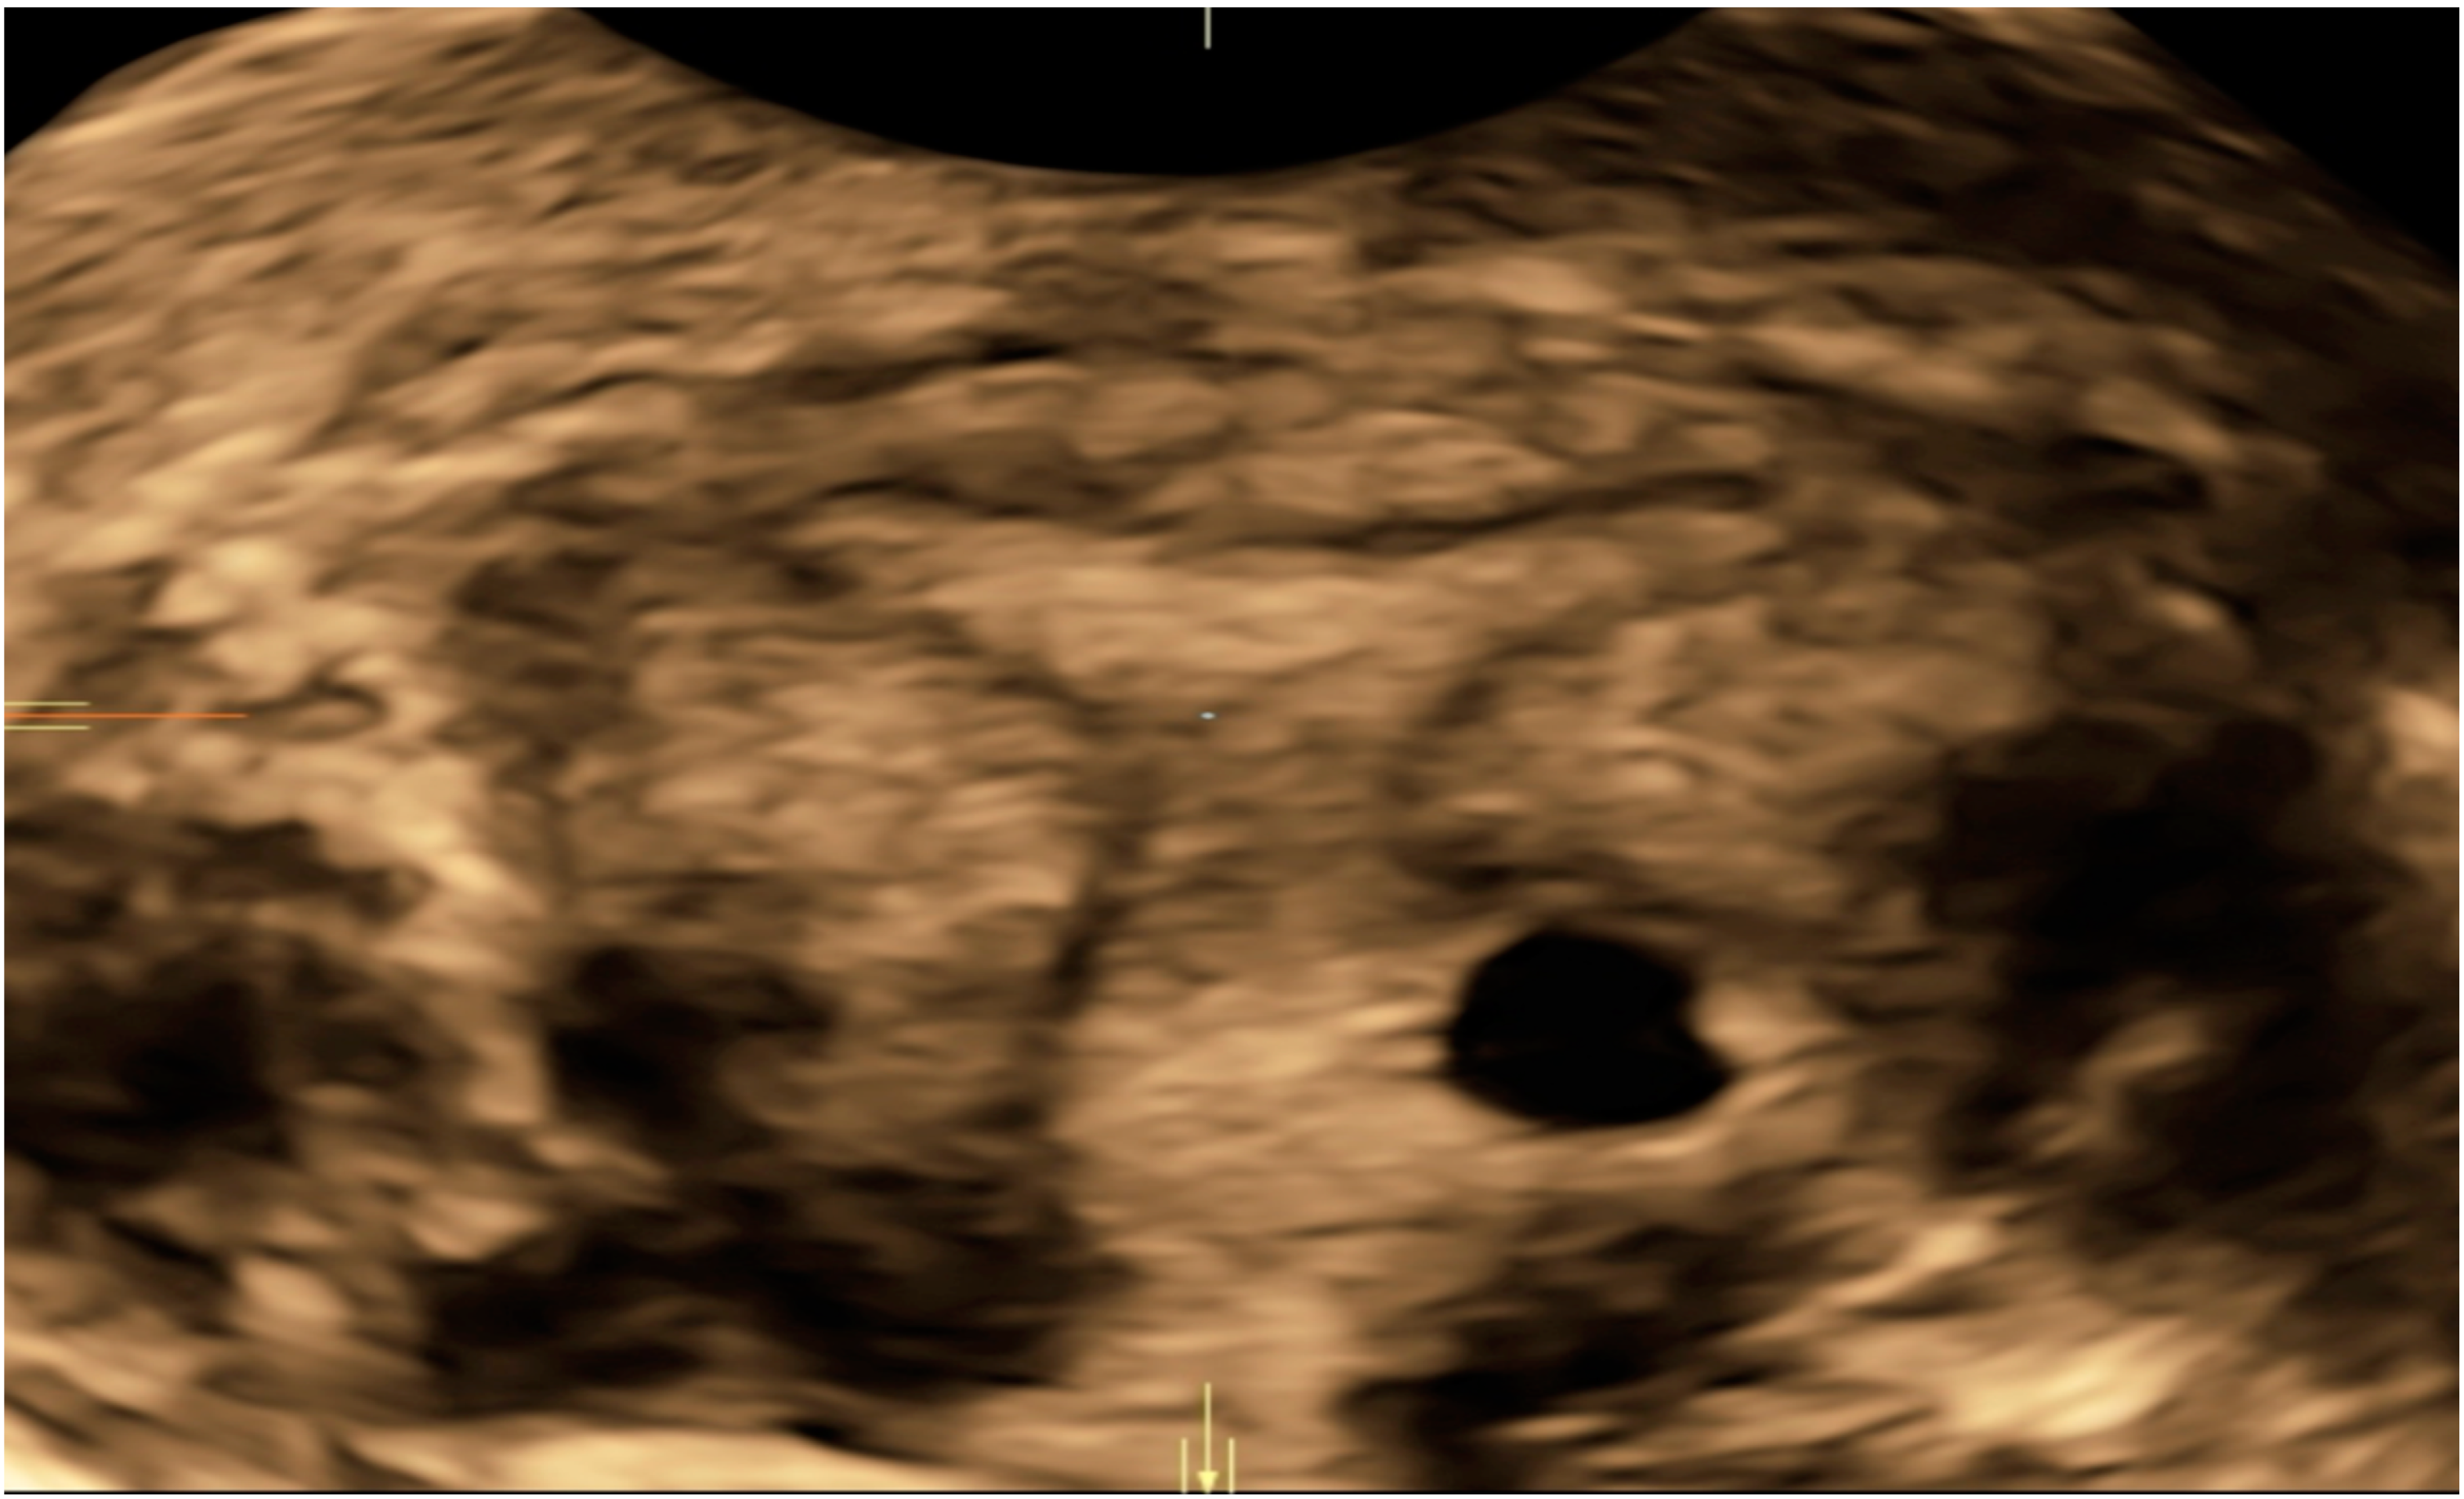

| Case 1 | Asymptomatic | 12 + 1 | 97,388 | GS 78 × 60 mm; with embryo | Radical surgical treatment (LPS hysterectomy + bilateral salpingectomy + uterine arterial embolization + bilateral ureteral stent placement) | Complete resolution |

| Case 2 | Asymptomatic | 6 + 6 | 10,862 | GS 20 × 19 mm; with embryo | Hys: 1st step: CP resection by twizzle; IC Foley catheter 2nd step: vessels electrocoagulation by bipolar twizzle | Reoperation (hys) due to tissue residues and cervical laceration Complete resolution |

| Case 3 | Asymptomatic | 5 | 9747 | GS 20 × 22 mm; no embryo | MTX IM 50 mg/m2 of body surface + Hys | Complete resolution Currently pregnant (PMA Homologous) |

| Case 4 | Brownish vaginal discharge | 6 + 6 | 55,951 | GS 30 × 10 mm; no embryo | Hys | Complete resolution |

| Case 5 | Vaginal bleeding | 9 | 1331 | GS 4.7 × 5 mm; no embryo | Mifepristone 600 mg orally + Misoprostol 400 mcg + MTX IM 50 mg/m2 of body surface | Complete resolution |

| Case 6 | Vaginal bleeding | 6 | 4274 | GS 5.4 × 5 mm with embryo | MTX IM 50 mg/m2 of body surface + Hys: CP resection by twizzle | Complete resolution |